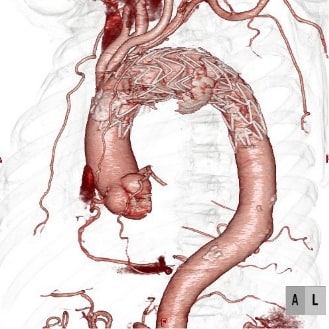

手術治療には、瘤を切り開いて人工血管に取り替える方法【人工血管置換術】と、瘤の中に金網付き人工血管(ステントグラフト)を通す【ステントグラフト内挿術】があります。

小さな創で治療可能な血管内治療を行います。また、瘤自体は残りますが、退院後の外来通院中に瘤が小さくなることが期待できます。

- 人工血管置換術とステントグラフト内挿術にはそれぞれ一長一短があります。年齢、瘤や解離の部位などを考慮してご相談の上、手術方法は選択します。

大動脈手術では、このシステムを利用して積極的に低侵襲治療である血管内治療(ステントグラフト内挿術)を行っています。腹部大動脈瘤だけではなく、弓部に至る胸部大動脈瘤でも、外科的処置を併用したステントグラフト治療を行なっております。